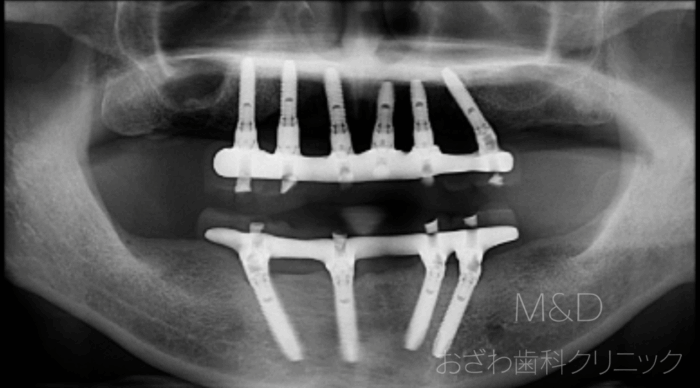

術後

上下顎残存歯の抜歯、上顎6本、下顎4本(オールオン4)インプラント

(上下顎即時負荷:オペの日に仮歯が入ります)

上顎 340万円(税別)、下顎 280万円(税別)